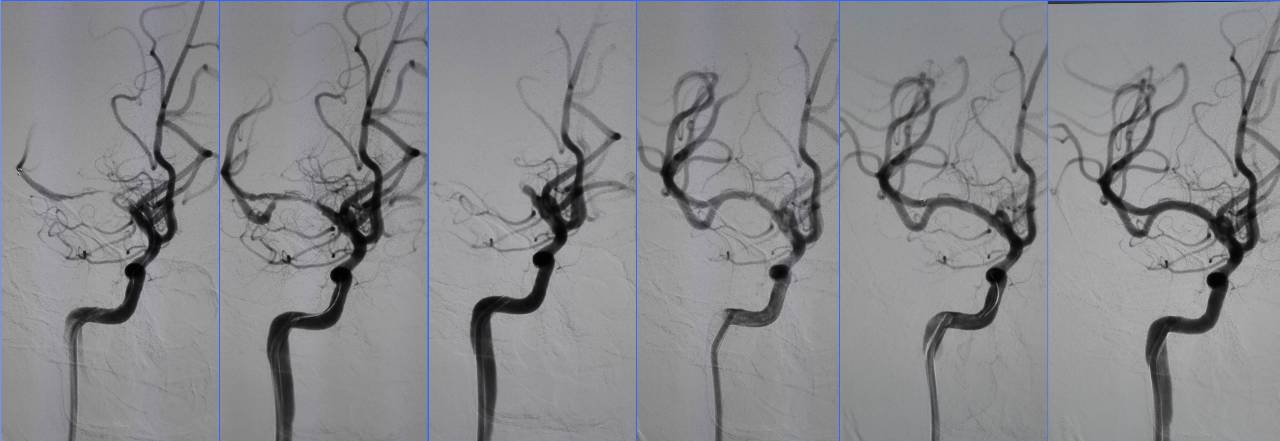

Case6 术后呼吸功能衰竭

》54岁,男,既往脑梗死、高血压病、糖尿病

》因头晕伴呕吐2天,9:50到达急诊

》10:08完成头CT检查

》15:30突发心跳骤停,行心肺复苏、气管插管

》NIHSS 30分

》15:55头MRA检查

》17:00行股动脉穿刺

》18:50结束手术

》术后24h NIHSS 10分

▼左椎动脉颅内段闭塞,脊髓前动脉代偿

▼右椎动脉颅外段闭塞

▼取栓后左椎动脉V4段残留狭窄

▼球囊成形,狭窄改善,不能维持

▼Wingspan支架置入

》11.30 13:00拔气管插管后不能呼吸,呼吸动度差,面部青紫,重新插管,spO2最低20%,意识不清,2小时后恢复。

》12.3 10:00再次拔管后仍不能呼吸,插管

》12.3 16:00行经皮气管切开。

》12.5 转普通病房后因血压高应用硝普钠后血压降至50mmHg,呼吸困难,青紫,昏迷,应用呼吸机后意识恢复。

》12.14自动出院,12.15死亡